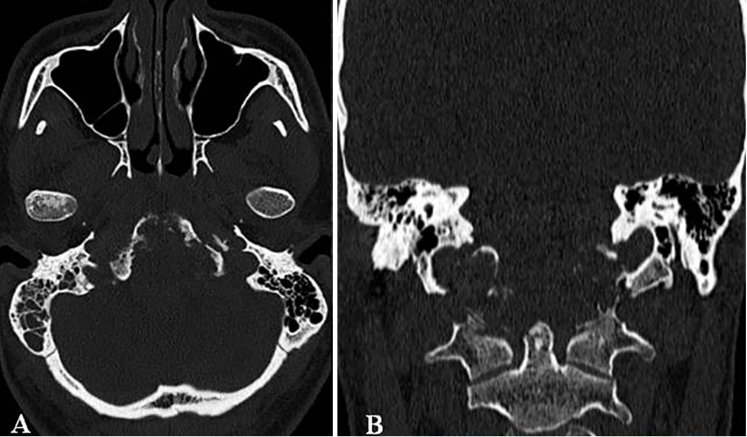

术前CT:显示颅颈交接区脊索瘤,侵犯斜坡-枕髁并呈溶骨性破坏。

MRI和CT扫描显示巨大颅颈交界区脊索瘤,肿瘤最大直径达10cm、瘤体积96.5cm³,肿瘤并向双后外侧延伸浸润性生长,较多侵犯右侧,肿瘤延伸至椎前间隙、下斜坡、双侧枕骨髁、第一颈椎C1的前弓以及C2的齿状突,巨大肿瘤压迫脑干和双侧椎动脉移位,并向硬膜内压迫扩张。